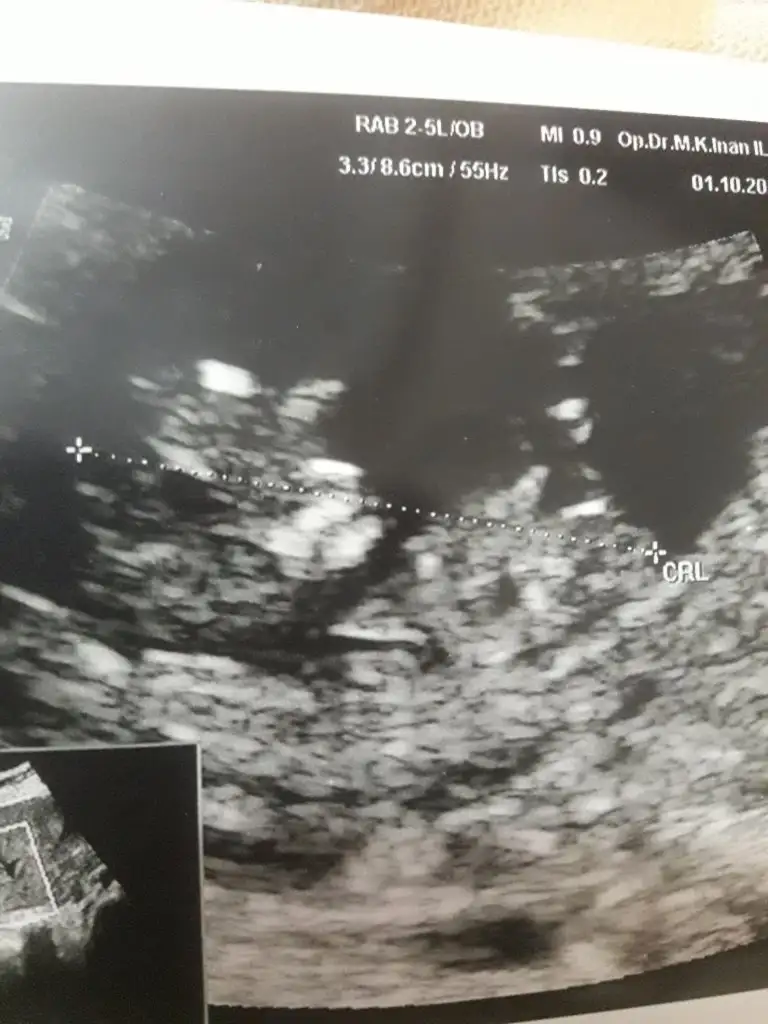

Evet 12 haftalikti, tekrar bakabilir misiniz rica etsemKaç haftalık büyük sanki USG 11 12 13 haftalar olmalı sanki sanki kız gibi tekrar USG paylasin

Bütün usgleri paylasirmisin varsa 11 12 13 haftalar olmalı haftalarında yazınErkek demişti ama haftaya kontrole gideceğim belki yanilmistir doktor diye sizlere de sormak istedim, çünkü çok erken bakmıştı

Burada nubu görünmüyor tatlım ama şekli bu defa kıza benzettim tabi nub önemli tekrar USG paylaşırsın

Çok teşekkür ederim geri dönüş yaptığın içinBurada nubu görünmüyor tatlım ama şekli bu defa kıza benzettim tabi nub önemli tekrar USG paylaşırsın![]()